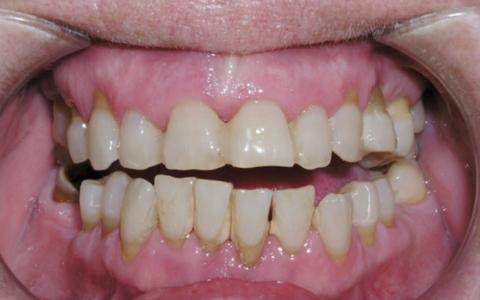

Paciente 50 años con grave problema periodontal. Severa pérdida de inserción y movilidad dental además de problema estético. Desea mejorar su sonrisa.

Plan de tratamiento: Rehabilitación maxilar con colocación de 10 implantes Microdent de conexión protésica interna del sistema Genius con cirugía guiada.